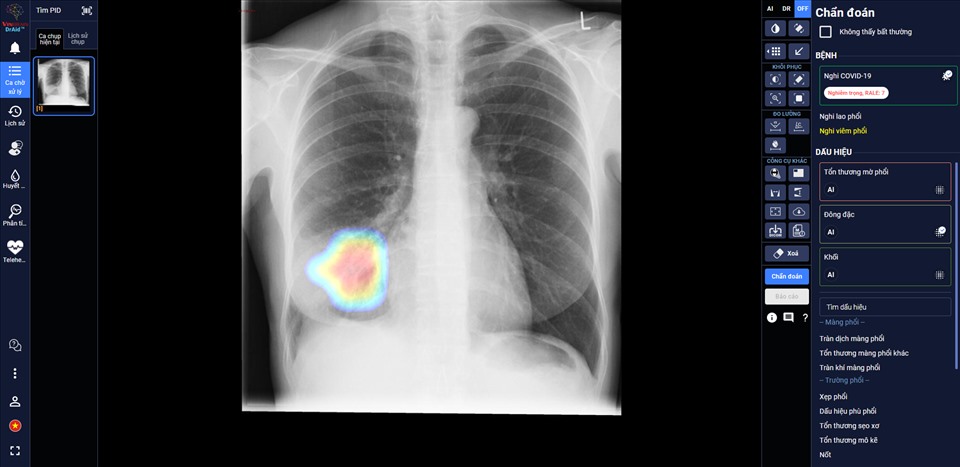

(VOVWORLD) - 先ごろ、保健省は、AI人工知能を新型コロナ感染者治療に導入する「新型コロナのドクターエイド(DrAid for Covid-19)」というソフトウェアを承認しました。

ベトナムの大手複合企業ビングループ傘下のVinBrain株式会社が開発したこのソフトウェアは、新型コロナ感染者の胸を撮影したレントゲン写真2万1千枚と普通の人の胸を撮影したレントゲン写真約12万を比較することによって感染者を発見できるとともに、患者の病症の評価及びこれからの動きを予測することができます。また、このソフトウェアは各病院のパソコンシステムに取り入れやすいとされています。

保健省は、全国の病院にこのソフトウェアの早期利用を提案しています。